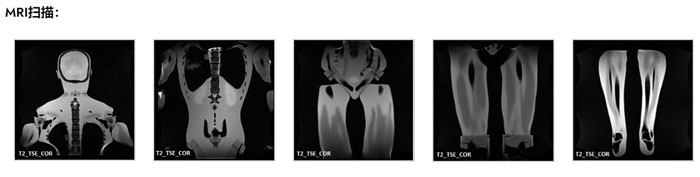

FB-A02成人全身模體,FB-A02全身CT模型成像效果圖如下:

FB-A02成人全身模體,FB-A02全身CT模型成像效果圖

在 MRI 應用方面,模型組織具有真實的 T2 弛豫時間值,這使得該產(chǎn)品最適合任何 T2 加權(quán) MRI 成像方法。質(zhì)子密度成像方法也可以獲得非常好的結(jié)果。模型仍然可以使用 T1 加權(quán)方法成像,但 T1 值不太真實,并且在大約 100 毫秒的范圍內(nèi)。